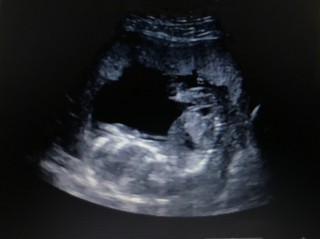

初めての体外受精で授かり、大量出血で切迫流産になり7~12wを寝たきりで過ごし、初めて4wあけての検診でした。背骨や肋骨もキレイ!!問題なく診察終わって看護師さんから「可愛いですね」と手渡されたエコー写真。何となく笑顔で手を振ってるような…(笑)今から親バカです(^^)